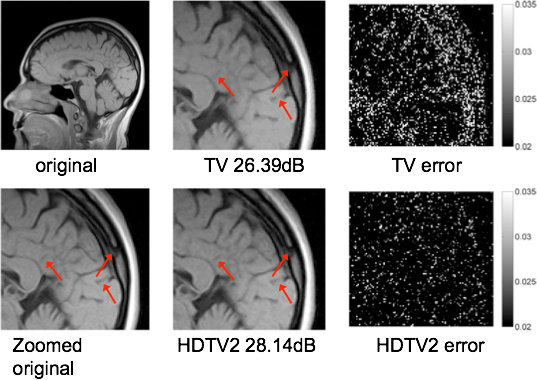

Higher Degree Total Variation (HDTV)

Total variation (TV) penalty

Brain MRI, acc=1.54, 25dB noise